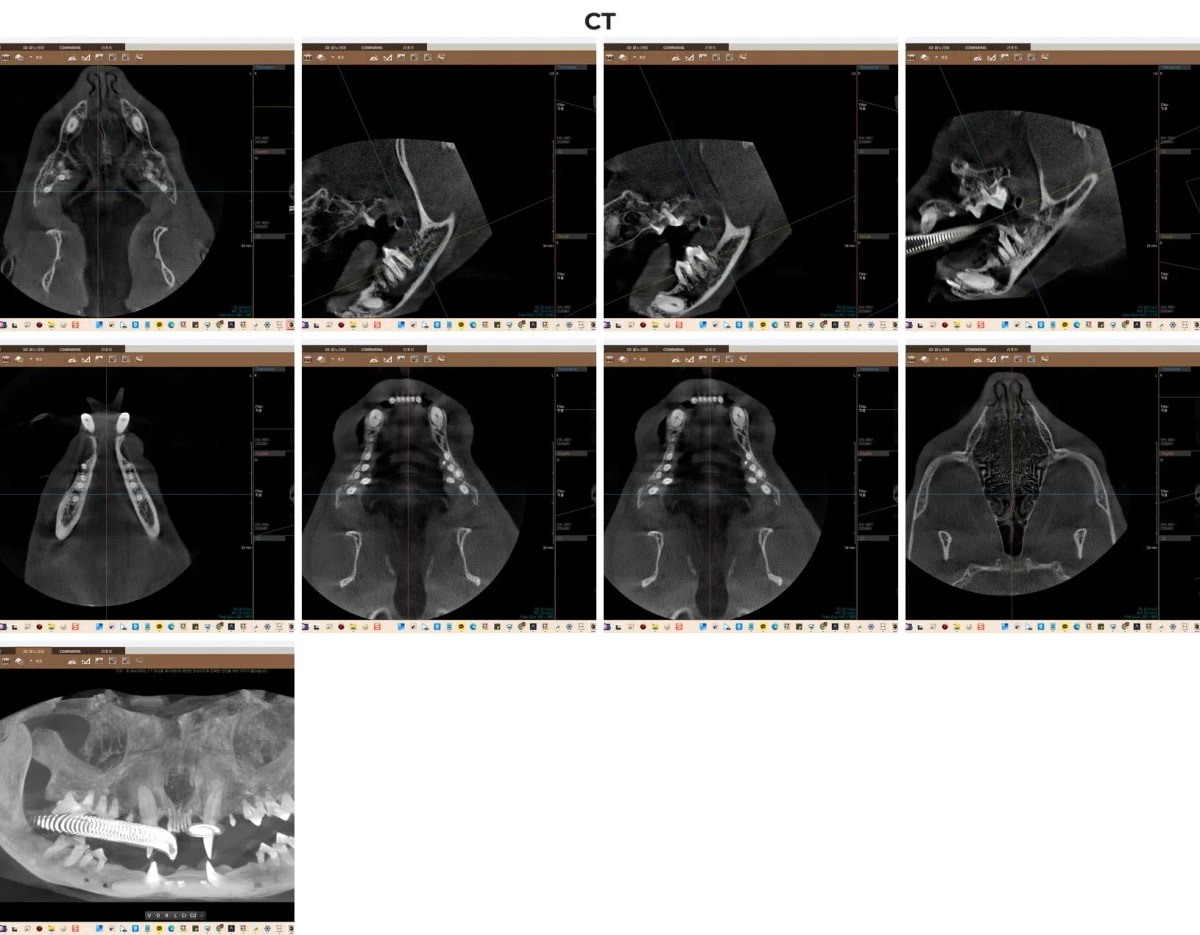

고양이 구내염 수술 시 겉으로 보이는 잇몸 염증뿐만 아니라, 턱뼈 내부로 파고든 치근(치아 뿌리)의 상태와 잇몸뼈(치조골)의 손상 정도를 입체적으로 파악하는 것이 필수적입니다. 광주 전남 유일의 동물전용 치과 CT를 통해 육안으로 보이지 않는 미세한 뼈의 밀도 변화와 숨은 뿌리 병변을 3D로 재구성하여, 수술 시 부러진 뿌리 조각 하나 없이 완벽하게 발치할 수 있는 내비게이션 역할을 합니다.

죽순이의 치조골 및 치근 상태를 파악하기 위한 치과 전용 CT 3D 촬영 소견